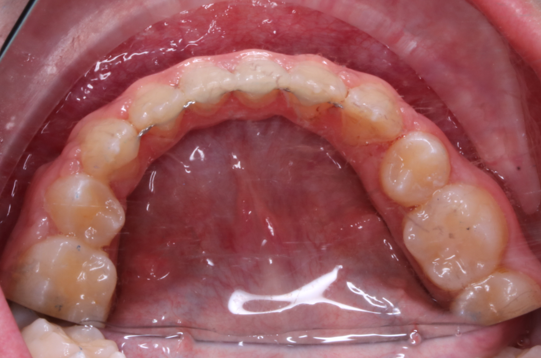

Llama la atención a primera vista la mordida abierta bilateral, especialmente pronunciada entre el cuadrante 1 y 4 debido a una interposición lingual en posición estática. Entre otros hallazgos fundamentales, observamos: un patrón dolicofacial severo (VERT: -2), una compresión de la arcada superior que cursa con un perfil y relación oclusal de clase III y la rotación del 35 y 45. Este caso se trató con un disyuntor, exodoncias de 44 y 34, brackets convencionales y educadores para rehabilitación de la lengua en un tiempo de 22 meses. Aunque estoy satisfecho con el resultado final, me hubiera gustado clavar la interscuspidación de premolares en el cuadrante I y IV, y mejorar la relación oclusal de cuadrante II y III. Sin embargo, lo bonito, es que hay a veces, en la ortodoncia real, que el paciente está satisfecho y quiere terminar antes de tiempo, o por el contrario, que el profesional intenta pero no consigue el resultado deseado. Y a mí más que compartir casos perfectos, me gusta mostrar mis errores, mi realidad.

DISCREPANCIA TRANSVERSAL DISYUNTOR MAXILAR

La ilustración nos deja entrever algo tan fácil como que en un paladar pequeño no entra una lengua grande. Y viceversa, en un paladar grande entra una lengua grande. Llevándonos dicha explicación al caso que nos atañe, podemos ver  en la fotografía lateral del lado derecho como la lengua escapa y busca espacio, de manera permanente, entre el cuadrante 1 y 4,  estímulo que mantenido en el tiempo generó en una mordida abierta lateral.